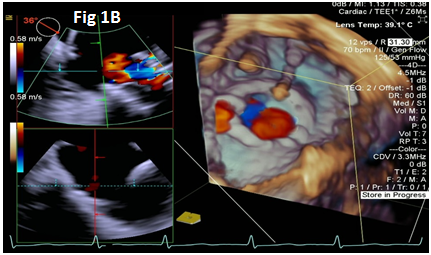

A 73-year-old female with mechanical mitral valve, tricuspid annuloplasty (32mm Edwards Physio Tricuspid incomplete ring) underwent Transcatheter Tricuspid Valve Replacement (TTVR) using off-label 29mm Edwards Sapien 3 (S3) Transcatheter Heart Valve (THV). Immediate post valve deployment, mild Perivalvular Leak (PVL) was noticed at the septal aspect (area of incomplete annuloplasty ring). Eighteen months later, patient presented with recurrent right heart failure and paracentesis due to severe tricuspid PVL (Figure 1A-C, Video 1). Percutaneous PVL closure under general anesthesia, Trans-esophageal Echocardiography (TEE) was performed. Via femoral venous access, defect was easily crossed with Agilis steerable sheath, multipurpose catheter and 0.035” glide wire. Despite recurrent attempts, wire came through the PVL but then traversed through open cells of S3 into the right ventricle (Figure 2A), confirmed with Armada 6mm balloon waist at the S3 cage (Figure 2B) (despite inflating 28mm Z med balloon inside S3 cage, Figure 2C). We decided to partially deploy the plug and assess valve function. Using 7.5F Asahi Eaucath multipurpose guide, a 12mm AmplatzerTM Vascular plug II (AVP II) was advanced through the defect. The ventricular disc was opened inside the S3 cage while body in the PVL defect (outside the S3 cage) and atrial disc on the atrial side of PVL (Figure 3A-B). With S3 function unaffected, no central leak and minimal gradient, PVL reduced to mild severity (Figure 4A-D, Video 2); the AVP II was successfully deployed (Figure 5). At 3-month follow up, there was an excellent symptomatic improvement (NYHA functional class I), with no heart failure re-hospitalization or paracentesis. Deployment of plug disc inside the valve frame is not recommended due to fear of interference with leaflet function and possible injury in long term. There was no immediate issue with the valve function in this case (due to space between the leaflet and frame of S3 and depends on size of plug used). Valve-in-Valve (S3-in-S3) would have certainly sealed all open cells treating this PVL but is more expensive option.

Figure 1 Para-valvular leak shown by color Doppler (1A) on 2D and 3D (1B) images, along with dense tricuspid spectral Doppler signal with peak velocity of 3m/s (1C).